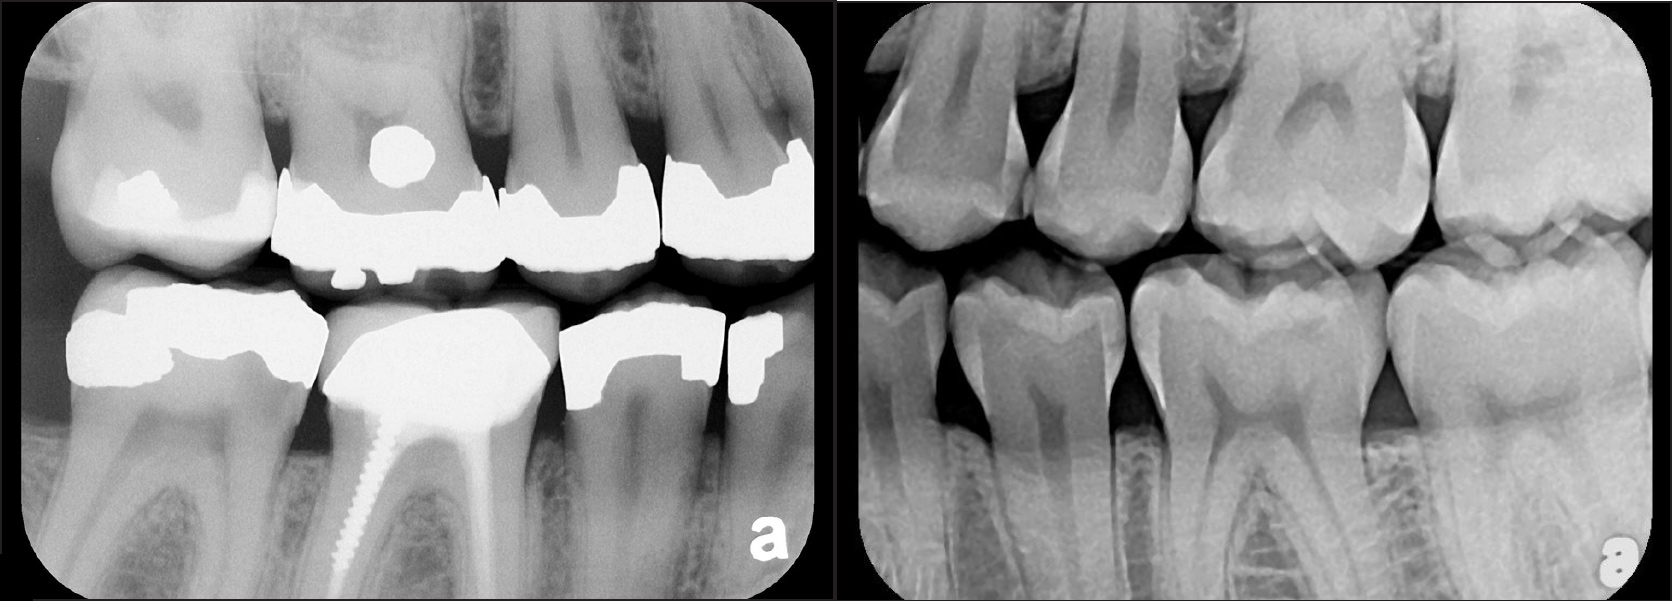

There are two specific types of DIDR sensor systems available to dentists in the marketplace: the hard-wired (HW) sensor and the photostimulable phosphor (PSP) sensor,1,2 also commonly known as phosphor "plates." A desirable feature common to both modalities is the ability to expose either bitewing (BW) or PA radiographic images. The BW radiograph (Figure 1) is usually considered more appropriate for caries detection, whereas the PA (Figure 2) is diagnostic for several different anatomic and pathologic issues.7

Fig 2. Left: PSP vertical PA radiograph of

maxillary bicuspid area demonstrating full root structure, several millimeters of bony anatomy beyond apices and maxillary sinus. Tooth No. 4 may be

traumatized as periodontal ligament is widened. Right: PSP horizontal PA radiograph of maxillary bicuspid area. Tooth No. 12 shows widened apical

periodontal ligament presumably caused by deep restorative filling. Some loss of supporting bone is evident interproximally, especially pronounced

between tooth Nos. 14 and 15.

Figure 2